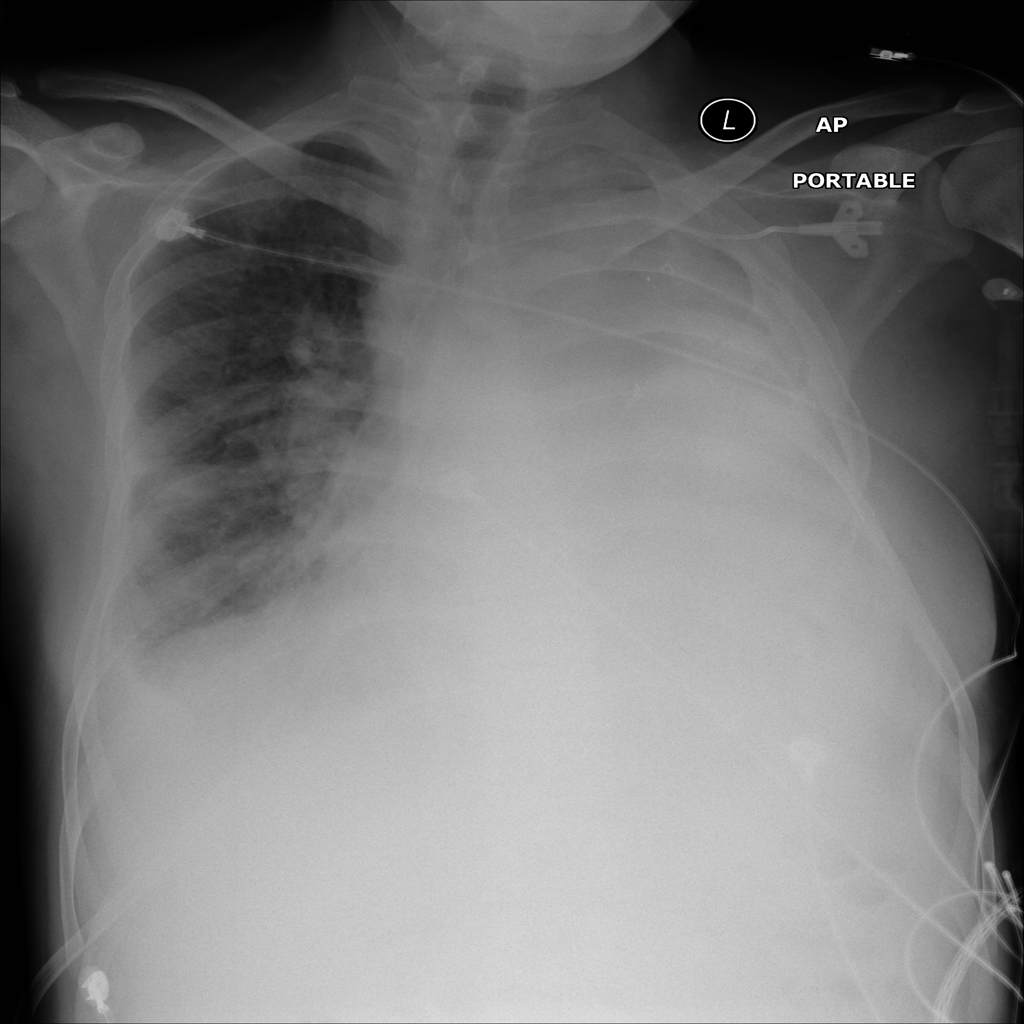

PAT-E81B · IMG-000Effusion

PAT-E81B · IMG-000

PA